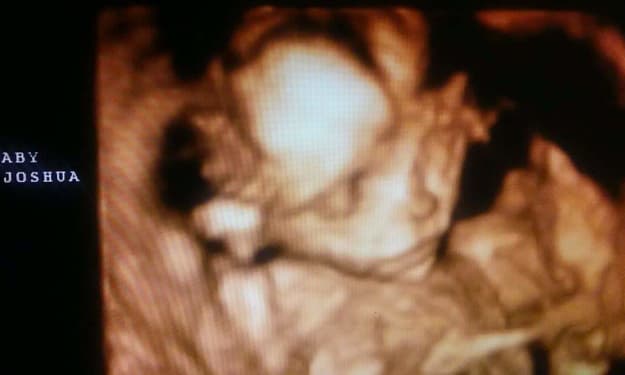

I have never had major surgery in my entire life. I was the most excited when I found out I was pregnant. I had a dream that someone had told me I was pregnant, and said, "Go take a test. You are pregnant." I was in denial because we had been trying for a while, but no luck. I was previously on the depo shot, which I hated. Anywho, I woke from the dream and took a test. It came up positive! I was so excited, nervous, and scared my husband would be upset. But he was just as excited.